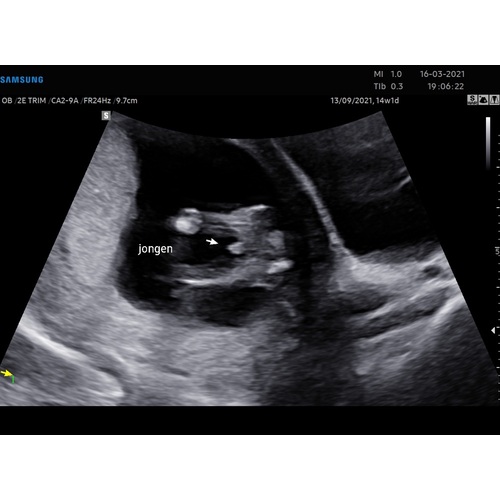

Dit was bij ons met 14 weken:)

Staat het pijltje niet verkeerd? Verder zie ik dat je 14 wk bent, dat is sws wel wat vroeg voor een geslachtsbepaling!!

Ja geen idee.. K ben inderdaad 14 weken. Maar ze garanderen het te kunnen zie :) Als het niet lukt, mag je terug komen.(bij mn andere 2 jongens ook gedaan met 14 weken, maar dat was zo duidelijk dat ik het zelfs zelf meteen zag)

Het middelste bobbeltje lijkt meer het piemeltje, vind je niet? T zou wel slordig zijn! 🙊 Ik heb helaas geen ervaring met echo's rond die termijn!